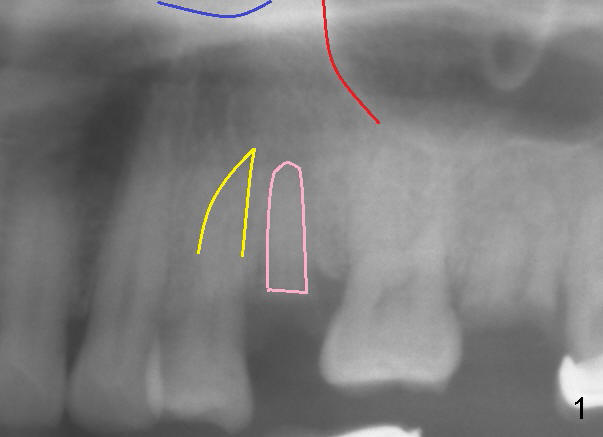

为什么能取得很好稳定性呢?第一,骨质密度高,第二,牙根长,第三,选择的植牙直径比牙根近远中宽度大,植牙植入时,紧紧与近远中骨壁接触(图四镜影像),舌侧间隙(箭头)几乎微不足道,颊侧间隙(B)大些,但不需要植骨或者放置membrane,做颊侧游离切口,然后与舌侧牙龈对缝,关闭伤口,最后用perio dressing保护伤口。由于车祸,术后十一个月病人才回治所复查,种植体正常。